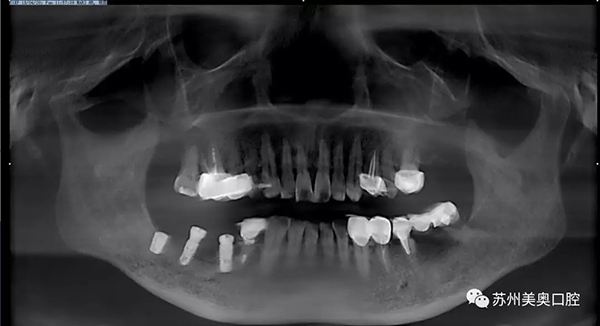

在美奥口腔种植之后,王阿姨目前的牙齿情况如下。